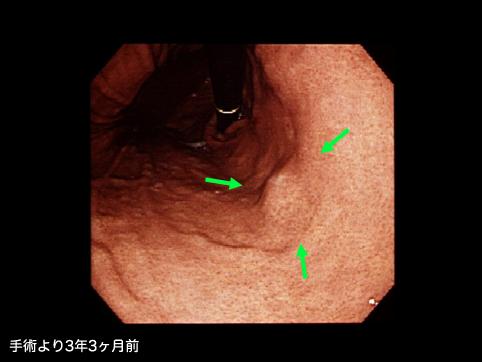

A case of gastrointestinal stromal tumor that extraluminally developed in size during four years and ten months.

악성 비상피성종양/평활근육종

위(부위)/체부

내시경

종양의 최대경(밀리미터)

10~14